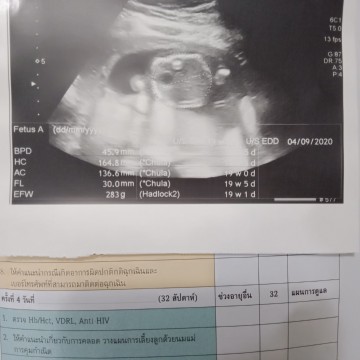

รูปซาวด์

สอบถามค่ะ นี่ส่วนไหนของลูกหรอค่ะ

ช่องท้องค่ะ ที่เห็นเป็นวงกลมดำๆข้างในคือกระเพาะค่ะ

น่าจะเป็นหัวนะคะ